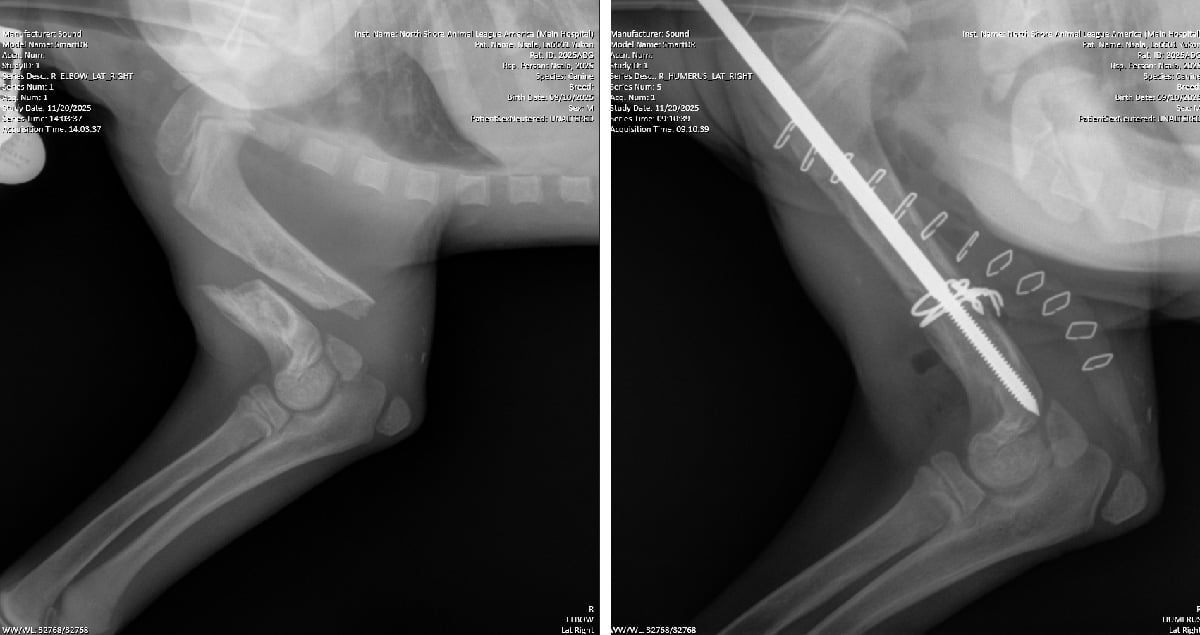

Yukon, a 4- to 5-month-old terrier mix, had suffered a fracture of the humerus that had been left untreated for at least two weeks. “The two ends of the broken bone were not even in the same zip code,” Dr. Verdino explained. He inserted a long metal rod down the center of the bone, secured it with wire, and carefully aligned the shattered pieces. Yukon had held his injured leg bent for so long that the ligaments and tendons contracted around it. “He does have motor function, so the prognosis is good,” Dr. Verdino said. “Once the bone heals, we can begin physical therapy to improve mobility. We’re optimistic he’ll regain some, if not all, function.”